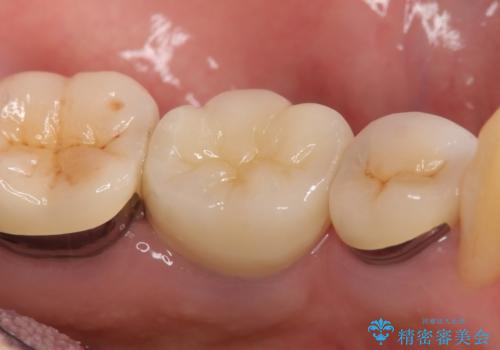

矮小歯 セラミッククラウンで綺麗に 30代女性

全顎的に歯並びにがたつきがあり、上の側切歯(上顎両側2)は生まれつき小さい歯(矮小歯)でした。

矯正治療後、矮小歯をセラミッククラウンにより理想的な歯の大きさに仕上げました。

自然な仕上がりにご満足頂けました。

「自分でもどこを治したのかわからないくらい自然!」と喜んで下さいました。

クラウンの種類:オールセラミッククラウン スペシャル